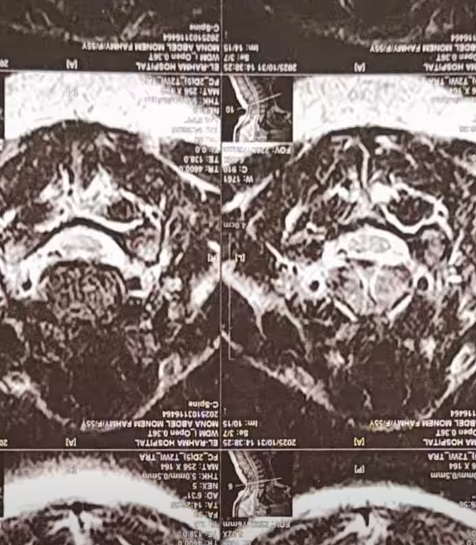

كشفت الإعلامية منى عراقي عن معاناتها في الفترة الماضية من أزمة صحية شديدة ، حيث أصيبت بمرض مناعي نادر مشيرة إلى أن الأطباء في مصر أكدوا لها أن المرض لا علاج له، وأنها ستضطر للعيش على العلاج الهرموني مدى حياتها .

وقالت منى عراقي  في فيديو نشرته عبر حسابها على فيس بوك : الدكاترة في مصر قالولي جالك مرض مناعي ملوش علاج، واللي هنقدر نعمله إننا نكتبلك علاج هرمون هتعيشي بيه باقية حياتك.

وأضافت منى عراقي : قعدت 3 سنين أجرب كل حاجة علشان أخف، لحد ما قابلت سيدة ألمانية كانت مصابة بنفس المرض، وقالتلي عالجي السبب الأساسي للمرض مش الأعراض.

وتابعت : بعد أربع شهور بدأت أتعالج، وسافرت الهند المكان اللي بيعالج بأسلوب الطب الشامل، من أول الروح والعقل والجسم مع بعض.